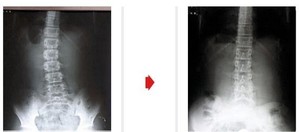

- 설명절 허리건강 지키는 법칙은 ‘10분’

- 노금종 2011.01.25

- 설 명절이 며칠 남지 않았다. 이에 명절 선물을 사고, 음식의 재료들을 준비하는 등 명절을 맡기 위한 움직임이 바쁘다. 그러나 설 명절이 누구나, 언제나 즐거운 것은 아니다. 스트레스와 고된 육체노동으로 인해 명절증후군에 시달리는 이 ...